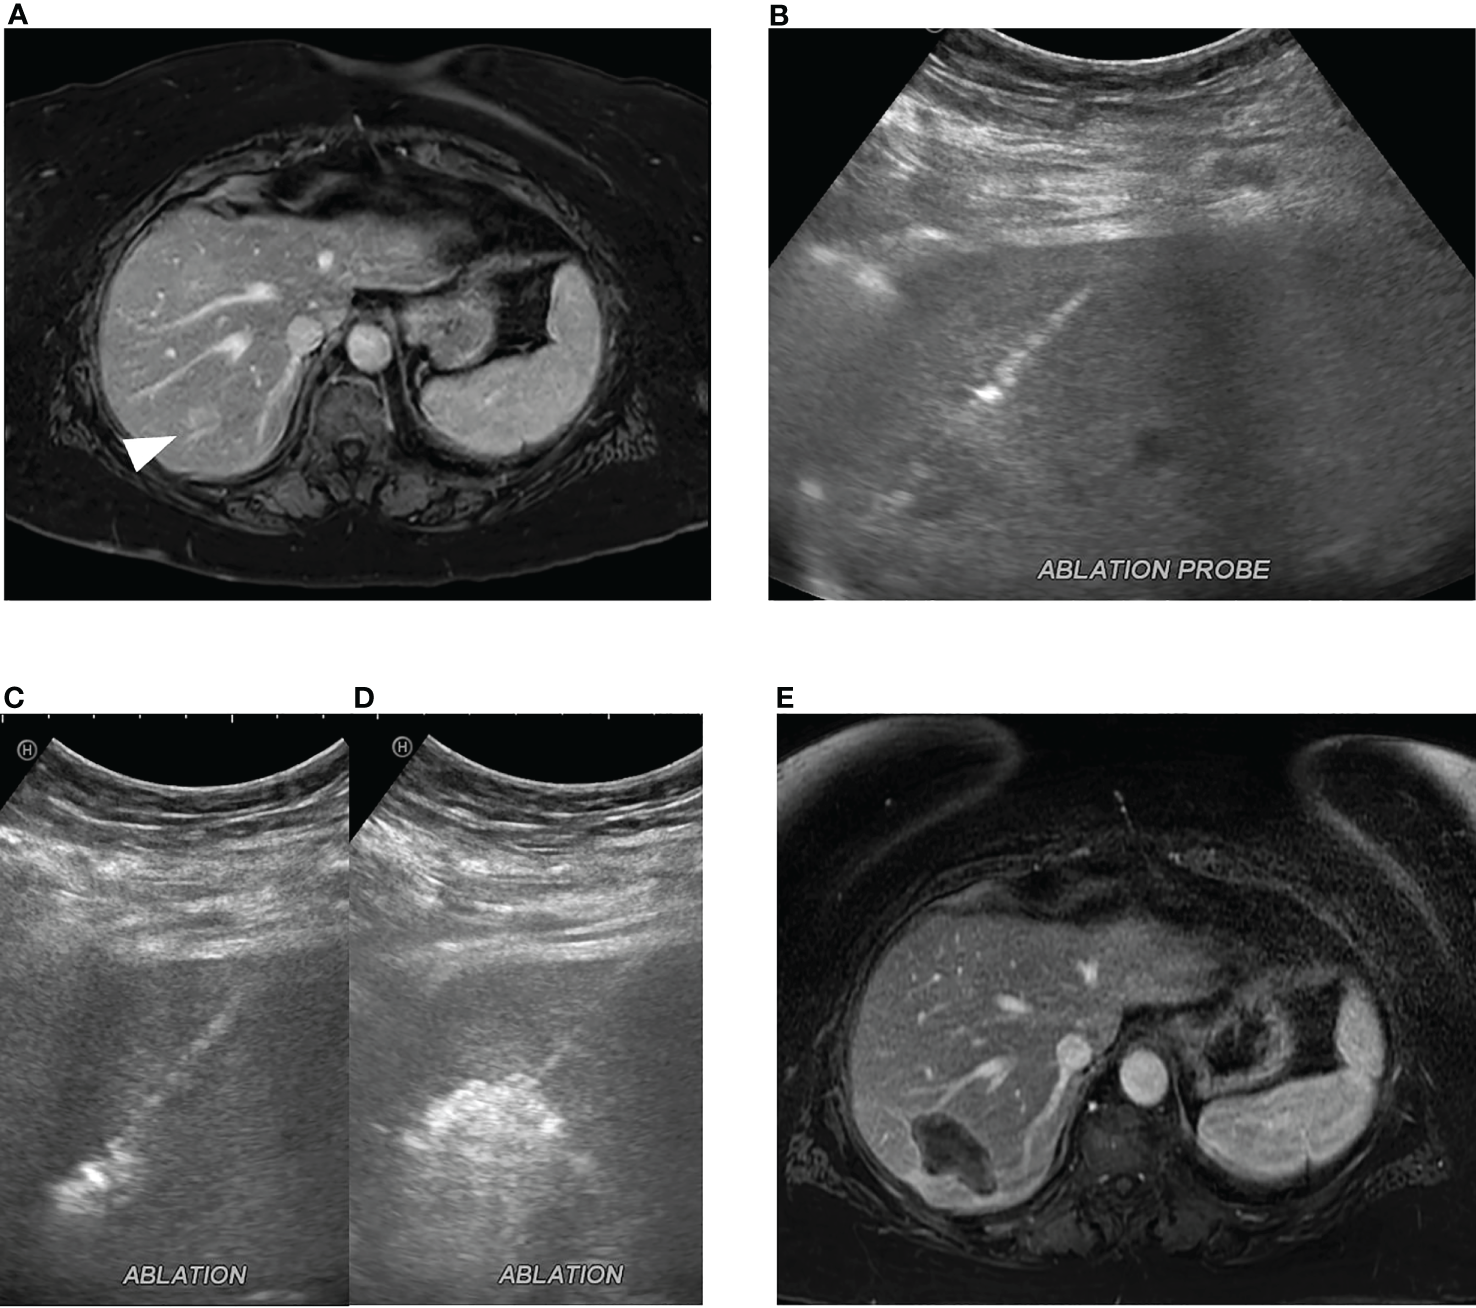

Figure 2

Microwave ablation of colorectal cancer liver metastasis. (A) A 2.0 cm colorectal cancer metastasis in segment 7 (white arrowhead). (B) Ultrasound-guided microwave ablation probe placement in the segment 7 lesion which was confirmed with CT (not shown). Continuous monitoring of ablation was performed with ultrasound with (C) early and (D) late ablation images obtained. (E) Post-ablation MRI, 1 month post procedure, demonstrates ablation zone without evidence of residual disease.